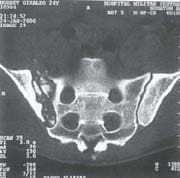

Fig. 4B Tomografía axial computarizada que evidencia luxofractura sacroiliaca.

De acuerdo a la clasificación AO para trauma pélvico, todos los pacientes se diagnosticaron como Tipo C. El tipo de lesión traumática más frecuente fue luxofractura de la articulación sacroiliaca, 10 pacientes (46%); de éstos, 6 pacientes (25%) derechos y 4 pacientes (21%) izquierdos (figuras 4A – 4B – 4C – 4D).